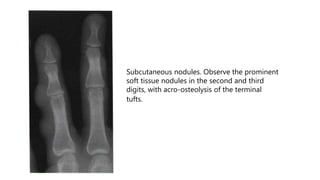

Subcutaneous nodules. Observe the prominent

soft tissue nodules in the second and third

digits, with acro-osteolysis of the terminal

tufts.